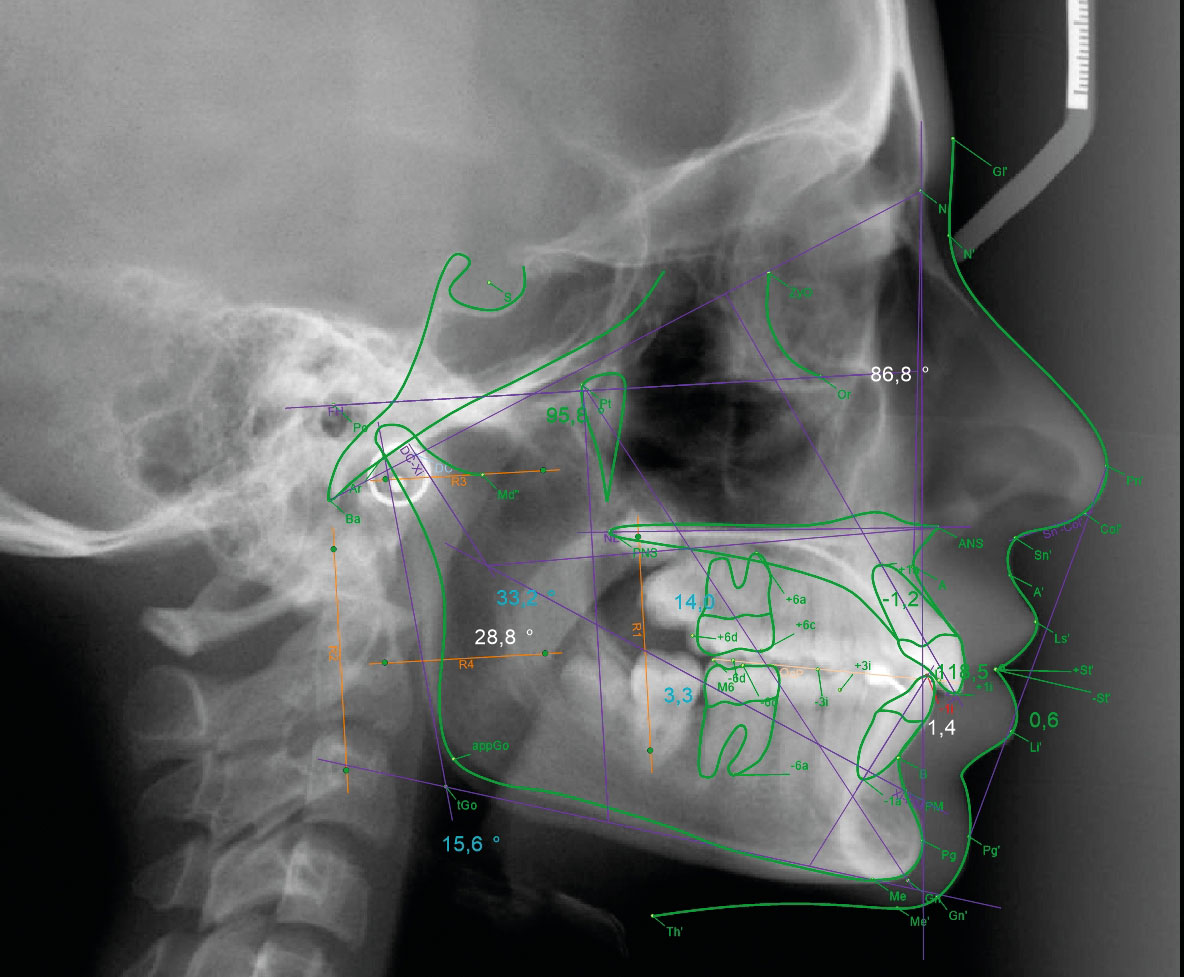

Avant de débuter le traitement, un bilan orthodontique doit être réalisé. Il se compose des examens complémentaires suivants :

- Examens radiographiques (radiographie panoramique et téléradiographie de profil)